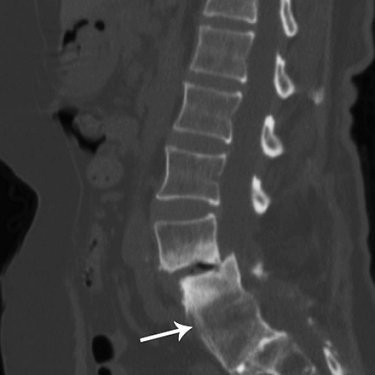

| A 65-year-old woman with history of L4-L5 fusion and anterolisthesis of L3-L7. Sagittal multiplanar reconstruction shows complete fusion (arrow). |

Digital radiographs and MDCT images were analyzed independently of each other by two musculoskeletal radiologists. According to the results, MDCT showed no evidence of bone bridging in 32.6% of the cases. Partial fusion could be seen on MDCT in 53.5% of the cases and full fusion in 14%. More than half the patients had metal implants, which lead to minor artifacts on MDCT, the group stated.